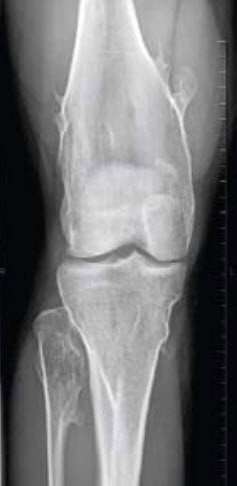

Abb. 2 zeigt ein typisches Bild der kartilaginären Exostosenkrankheit am Kniegelenk. Neben der deutlichen Verbreiterung der metaphysären Knochenanteile zeigen sich multiple Exostosen am distalen Femur, der proximalen Tibia wie auch am Fibulaköpfchen.